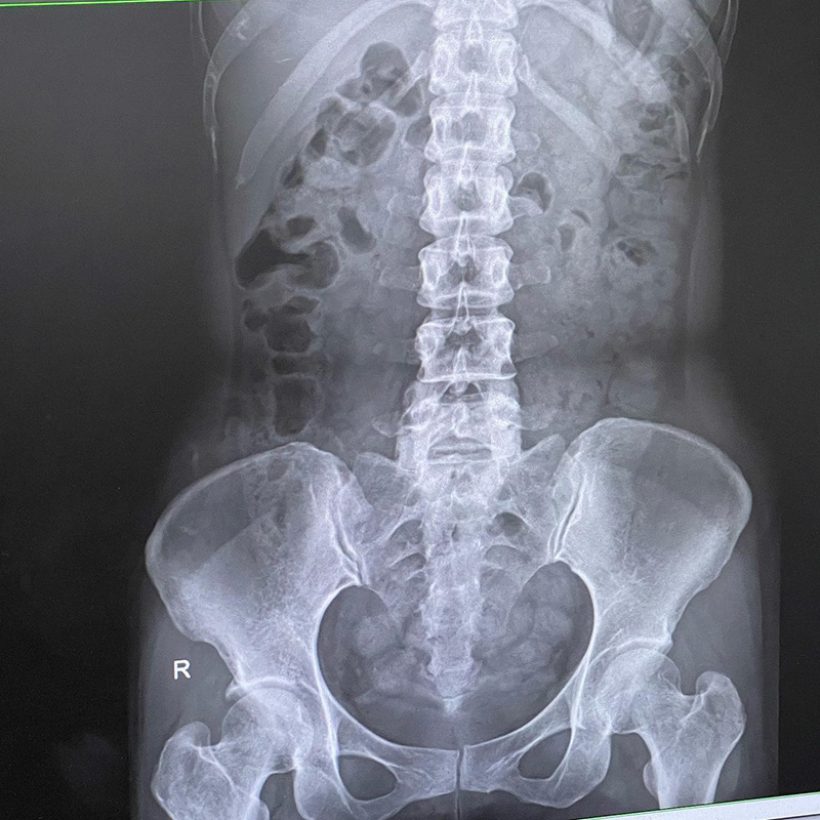

“เลื่อนขวา เพื่อดูฟิล์มเอ็กซเรย์ หลังจากที่หาหมอจนเจอว่าเป็นโรค (ขอเรียกว่าโรคละกัน) “ขี้เต็มท้อง” พอซัดยาหมอตามอาการเข้าไป วันรุ่งขึ้นเท่านั้น ที่ลอตแรกได้ถูกปลดปล่อย >> ดีขึ้นทันตาเห็น >> ใช่ละ กรูเป็นหละ สาเหตุนี้

ในฟิล์ม ที่เห็นขาว ๆ ก็คือ ขี้น้อนทั้งนั้นเลยค่ะ ลอยละล่องเป็นยองใย เยอะแค่ไหนถามใจเธอดู”